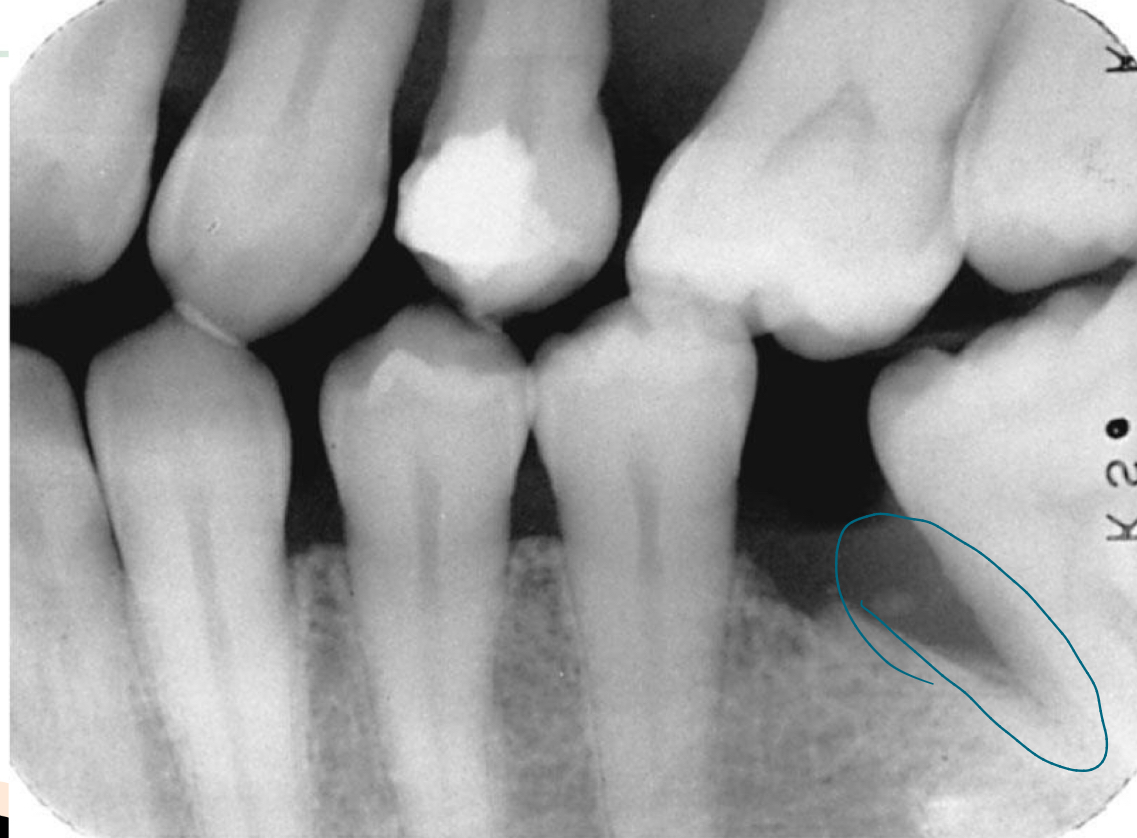

Bone loss

Difference between the physiologic bone level and height of remaining bone

Horizontal vs vertical

Vertical bone loss

Severity of bone loss

Slight, moderate , severe

Severe bone loss

5mm or more (33% or more)

Local irritants may contribute to: calc, defective restorations

Nodular calc